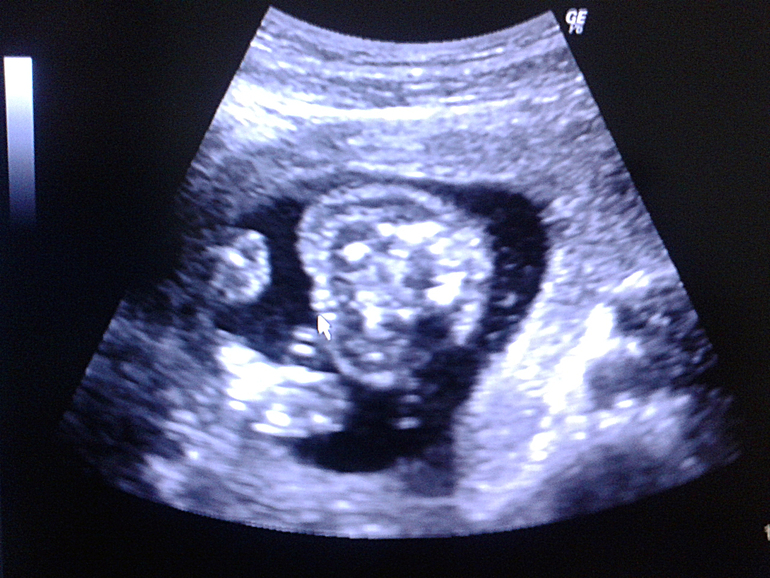

Сегодня были на УЗИ! С крохой слава Богу все в порядке, только матка у меня как сказала врач реагирует на малейшее движение сильным тонусом, так что увеличили нам дозу лекарств и опять постельный режим.

А ТЕПЕРЬ О ГЛАВНОМ! У НАС БУДЕТ 100% ДОЧЕНЬКА! ))) Весим мы сейчас 370 гр, рост что-то я прошляпила, засмотрелась на маленькие ножки ))